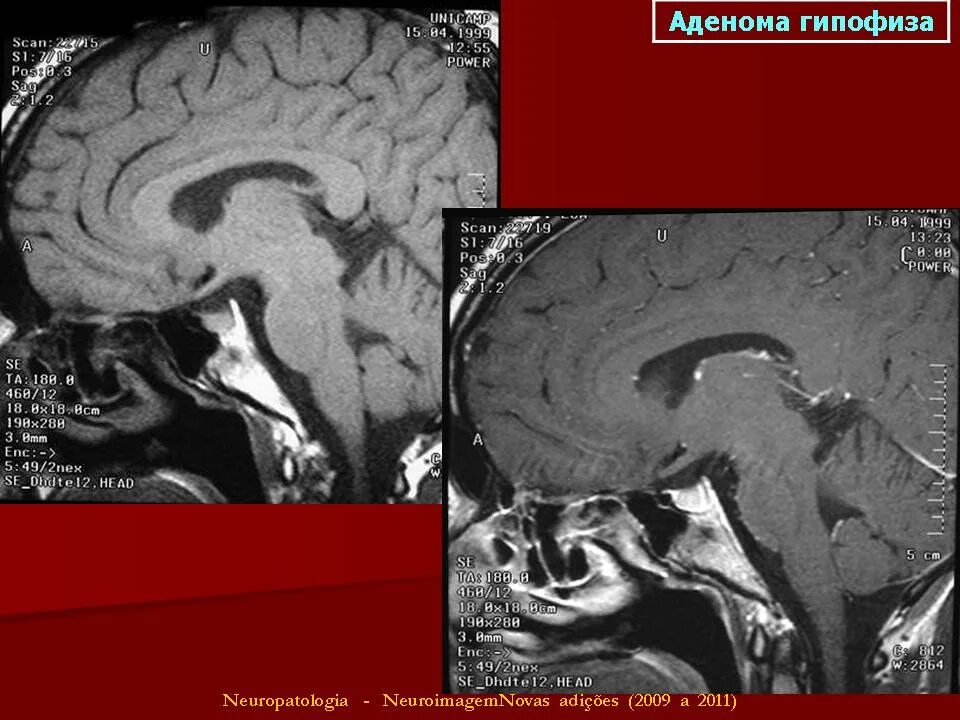

Опухоль гипофиза